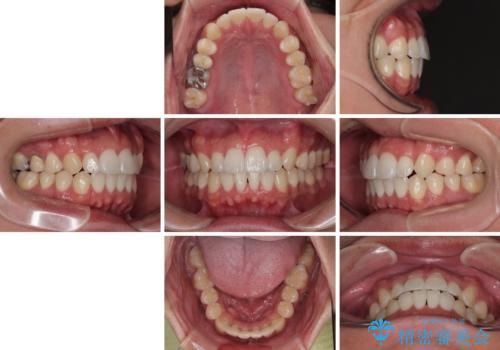

前歯のデコボコをささっと治す 短期間でのインビザライン矯正治療

- 前歯の反対咬合などを気にして来院された患者様です。

ワイヤー矯正、マウスピース矯正どちらでも対応可能であったので、ご本人の希望によりインビザラインにて矯正治療を行うこととしました。

毎日の装着時間をしっかりと守ってくださり、1年強の短期間で、あっという間に治療を終えることができました。